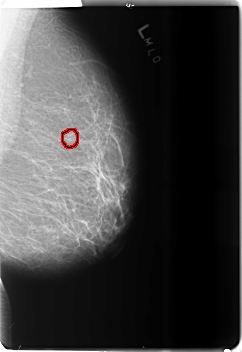

B_3494_1.LEFT_MLO

B_3494_1.LEFT_CC

FILE: B_3494_1.LEFT_MLO.OVERLAY

TOTAL_ABNORMALITIES 1

ABNORMALITY 1

LESION_TYPE CALCIFICATION TYPE PLEOMORPHIC DISTRIBUTION CLUSTERED

ASSESSMENT 4

SUBTLETY 3

PATHOLOGY BENIGN

TOTAL_OUTLINES 1

BOUNDARY

FILE: B_3494_1.LEFT_CC.OVERLAY

LESION_TYPE CALCIFICATION TYPE ROUND_AND_REGULAR-AMORPHOUS DISTRIBUTION N/A